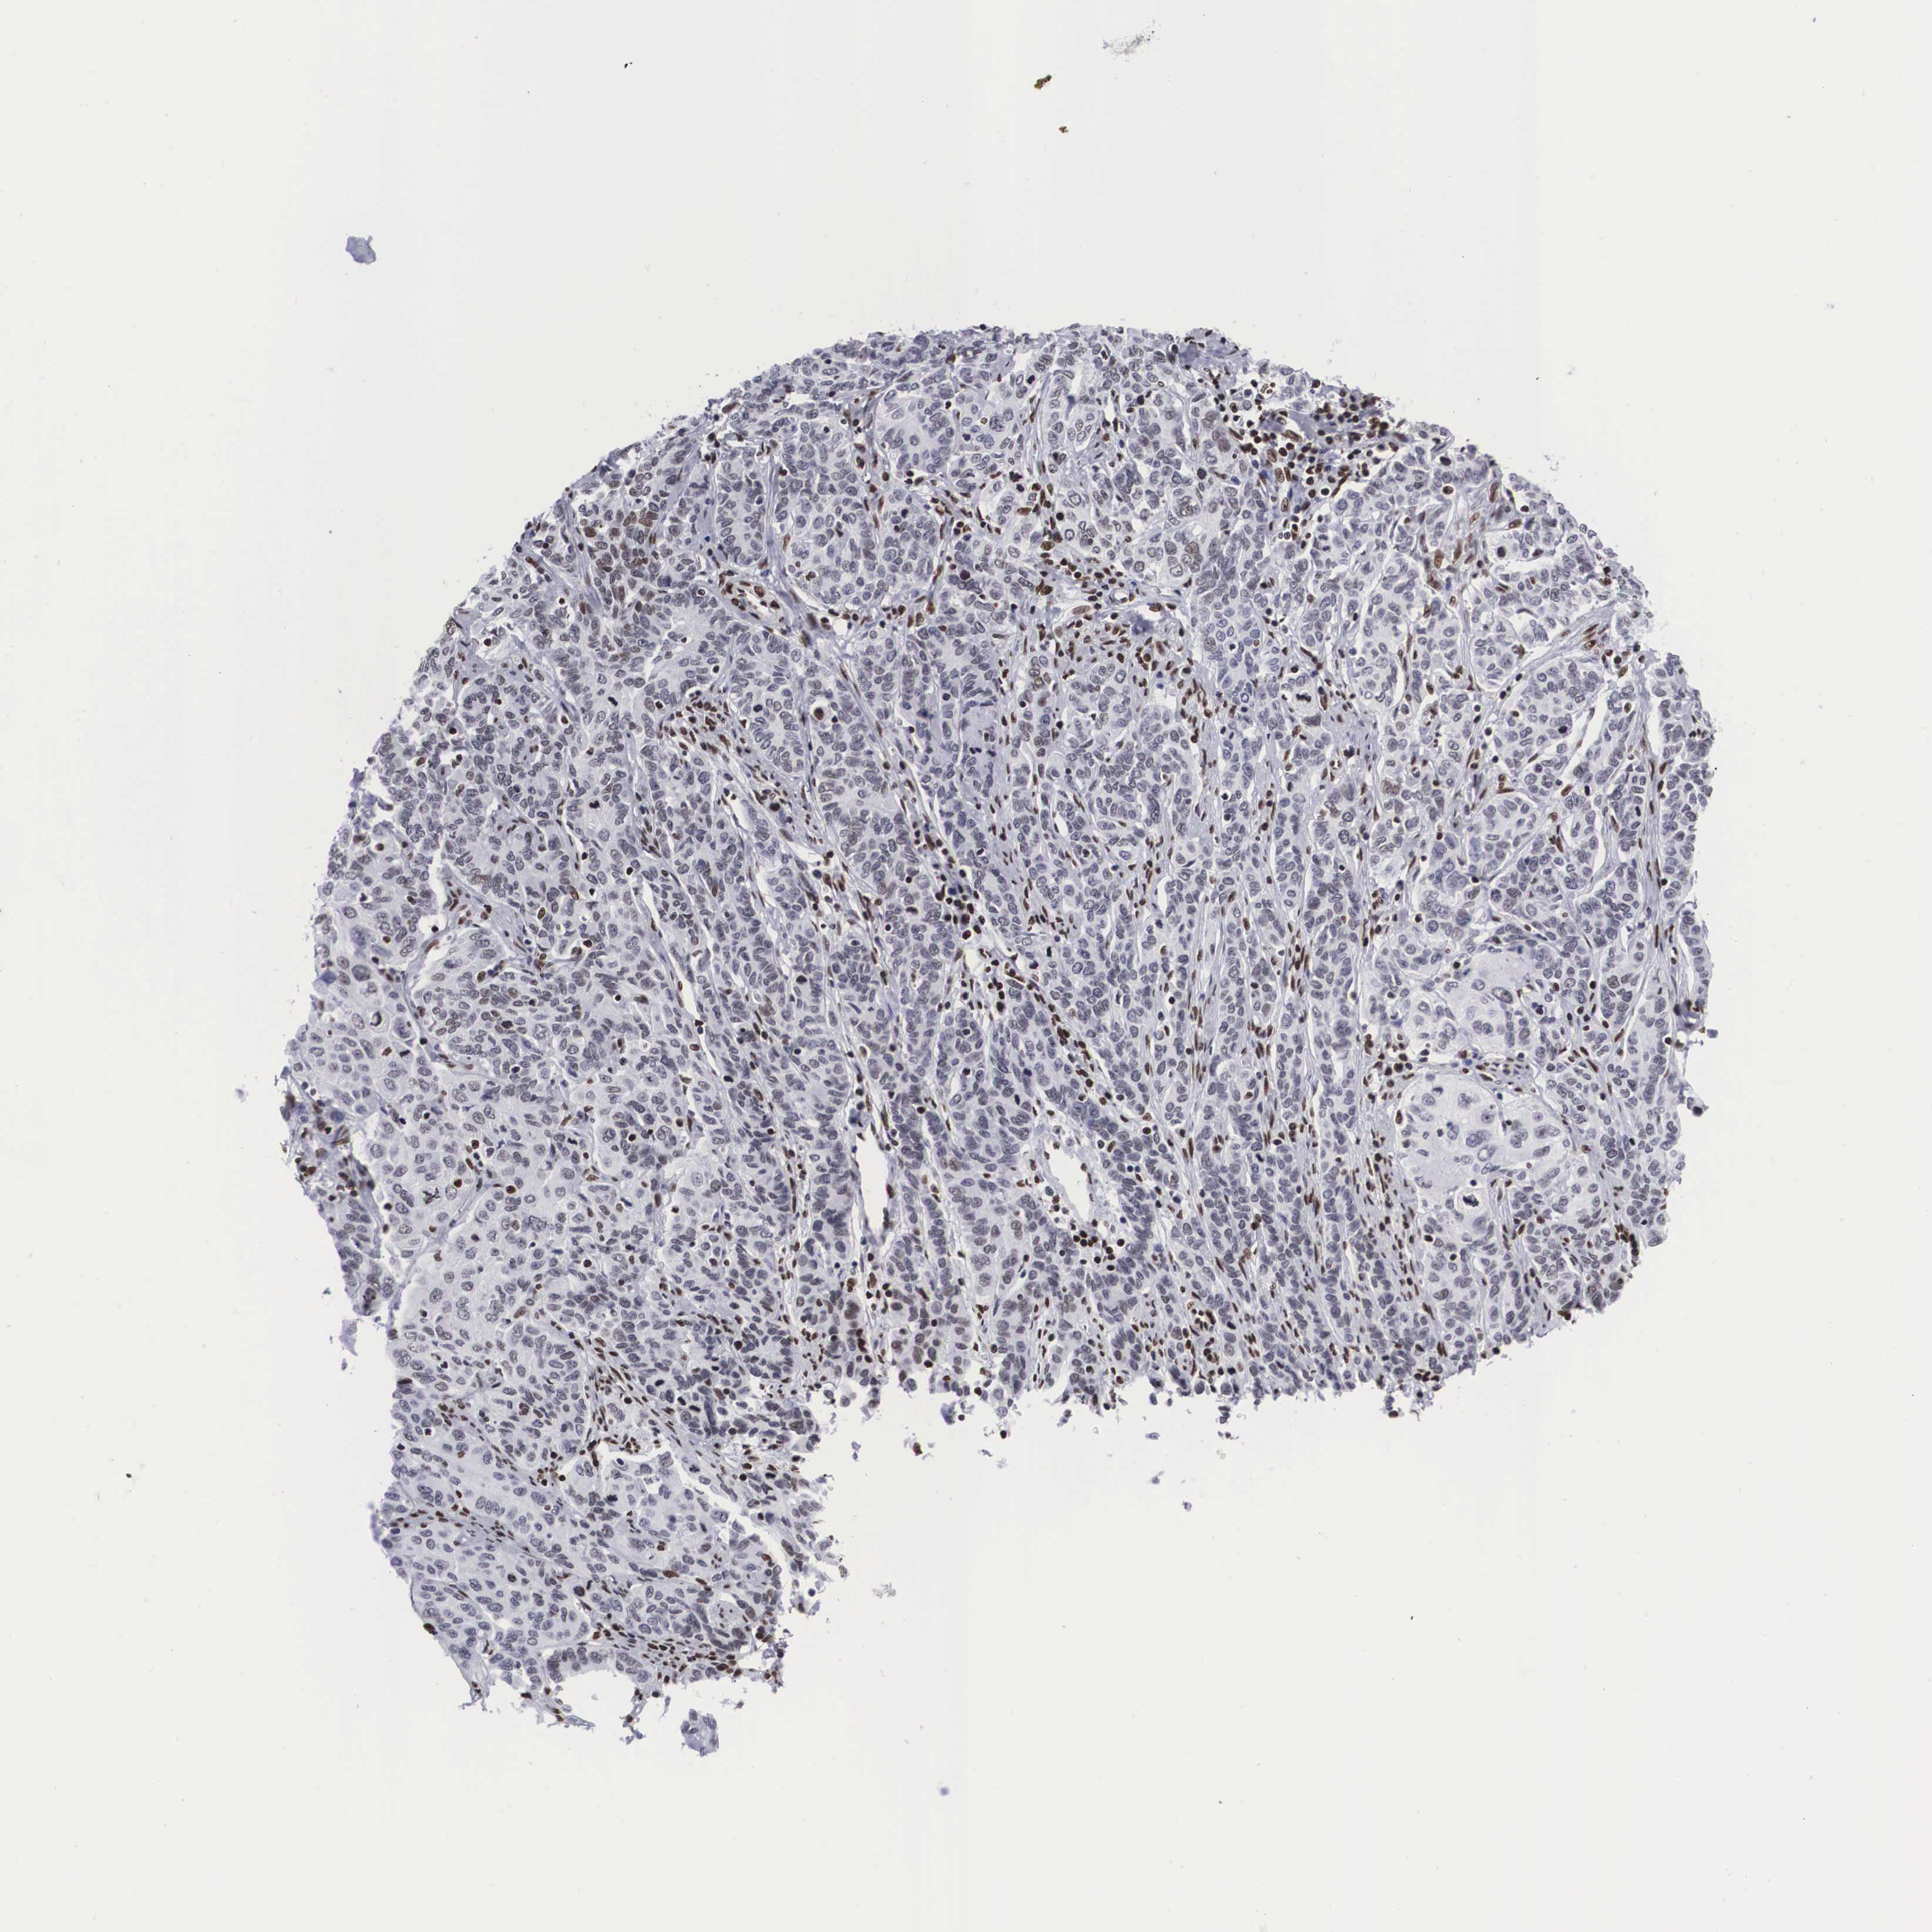

CERVICAL CANCER - Protein expressioni

A mouse-over function shows sample information and annotation data. Click on an image to view it in a full screen mode. Samples can be filtered based on level of antibody staining by selecting one or several of the following categories: high, medium, low and not detected. The assay and annotation is described here.

Note that samples used for immunohistochemistry by the Human Protein Atlas do not correspond to samples in the TCGA dataset.

Antibody stainingi

Antibody staining in the annotated cell types in the current human tissue is reported as not detected, low, medium, or high, based on conventional immunohistochemistry profiling in selected tissues. This score is based on the combination of the staining intensity and fraction of stained cells.

Each image is clickable and will lead to virtual microscopy that enables deeper exploration of all samples and also displays staining intensity scores, fraction scores and subcellular localization as well as patient and tissue information for each sample.

Antibody HPA000593

Antibody HPA001341

Antibody CAB037264

Staining

High

Medium

Low

Not detected

Intensity

Strong

Moderate

Weak

Negative

Quantity

>75%

75%-25%

<25%

None

Location

Nuclear

Cytoplasmic/membranous

Cytoplasmic/membranous,nuclear

Adenocarcinoma, NOS

Squamous cell carcinoma, NOS